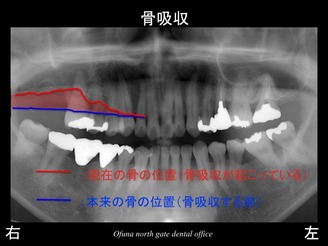

いつものように 骨吸収の状態を分かりやすくするために

骨吸収の状態を線で書いたのが以下のレントゲンになります。

青線が骨吸収を起こす前の骨の位置です。

赤線は、現在の骨の位置です。

さらに分かりやすくするために 骨吸収部位を赤色の領域で表します。

骨吸収が非常に進行しているのが分かるかと思います。